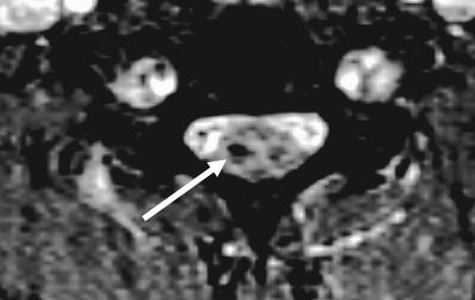

МРТ шейного отдела позвоночника. Аксиальная Т2-взвешенная МРТ. Кровоизлияние в спинной мозг.